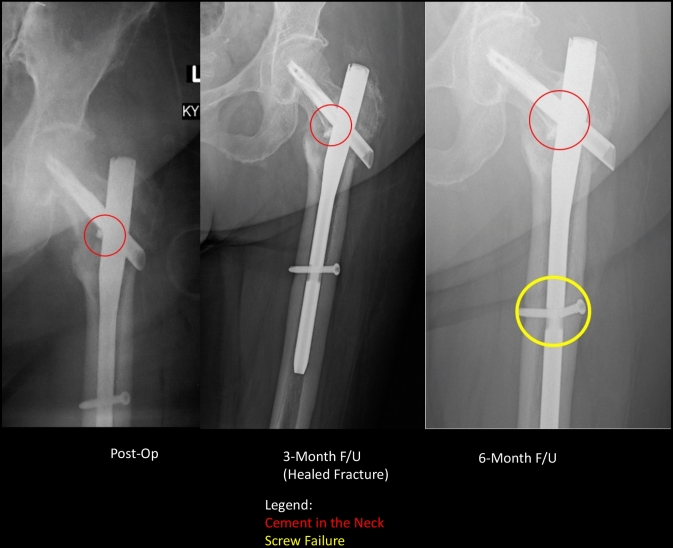

Fig. 3.

Comparison of position of the distal nail tip of the TFN-A (left) and the PFNA (right). The tip of the PFNA is noticeably more anterior and impinges on the anterior cortex

Anterior cortical impingement or perforation is attributed to the mismatch between the femoral bow and the nail geometry. Our study, wherein 23 patients were fixed with a long nail, had no incidence of anterior cortical impingement or blowout, which suggests that the TFN-A has a nail geometry that appears to more closely approximate the native femoral bow found in the Asian population [10, 11] (Fig. 3). In three patients with a pure diaphyseal fracture (AO/OTA 32.A3, the femoral bow was the factor noted to have influenced the surgeons to use the TFN-A as opposed to other implants more traditionally favoured for diaphyseal fixation. Clinical studies that attempt to compare the femoral bow with implant geometry are sparse [10, 11] and with the advent of the TFN-A, comparisons between it and more well-established implants may shed light on this relatively rare—but nonetheless severe—complication.